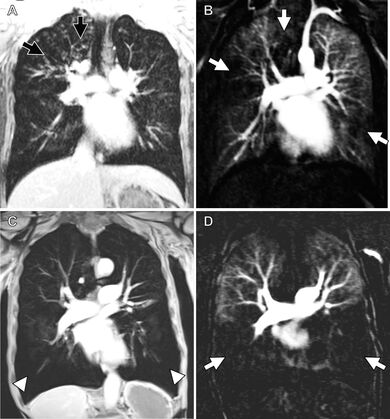

In addition to morphological imaging, MRI offers the possibility of additional functional information. Using dynamic MRI sequences, respiratory mechanics, lung ventilation and lung perfusion can be determined. These functional parameters enable conclusions to be drawn about the pathophysiology of the lungs and improve the imaging of diseases such as COPD, CF and pulmonary embolism. The combination of morphological and functional lung imaging with high spatial and temporal resolution is a major advantage of MRI compared to other imaging modalities. For example, approaches for quantifying perfusion defects were developed in this research group.

High-resolution MR angiography can also provide information about the pulmonary arteries and the bronchial arteries, which are often enlarged in chronic lung diseases.

- Wucherpfennig L, Triphan SMF, Wege S, Kauczor HU, Heussel CP, Sommerburg O, Stahl M, Mall MA, Eichinger M, Wielpütz MO. Elexacaftor/Tezacaftor/Ivacaftor Improves Bronchial Artery Dilatation Detected by Magnetic Resonance Imaging in Patients with Cystic Fibrosis. Ann Am Thorac Soc. 2023 Nov;20(11):1595-1604. doi: 10.1513/AnnalsATS.202302-168OC.